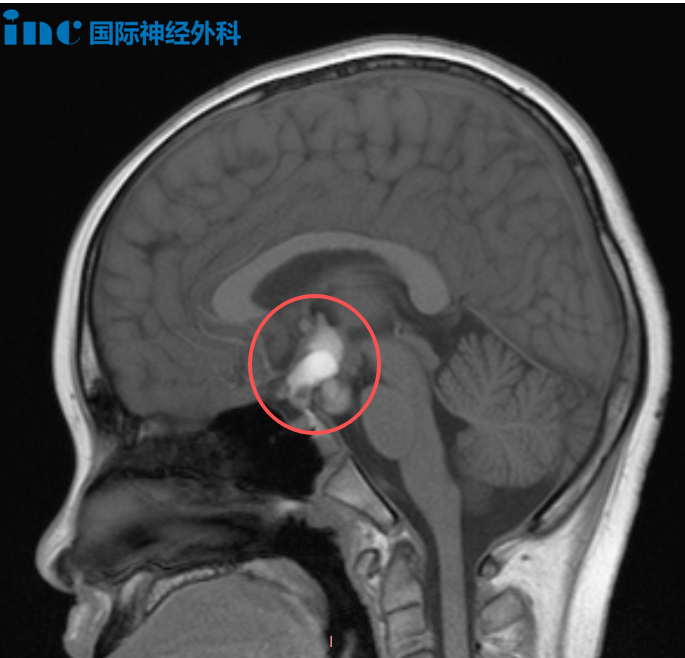

病例二:12岁男性颅咽管瘤

颅咽管瘤的可怕之处不仅在于其位置深在要害区域、手术难度极高,更在于它可能破坏儿童的生长发育、视力功能,甚至危及生命。医生需要在狭小空间内完成精准切除,0.1毫米的误差就可能改变一个孩子的命运。即使颅咽管瘤完全切除手术难度大、创伤大、并发症发生率高,手术仍是颅咽管瘤主要治疗手段。

12岁男性患儿涛涛今年8月因头痛检出颅咽管瘤,20mm×15mm×27mm大小的病变已导致脑干受压后移,压迫视交叉后方的视路系统。

颅咽管瘤手术首要目标是安全、彻底地抵达并切除肿瘤;其次要尽可能保留垂体柄。垂体柄是连接下丘脑与垂体腺的重要通道,垂体腺负责分泌激素,而下丘脑则像汽车的刹车和油门,调控激素分泌节奏,例如早晨皮质醇分泌量高于下午,这种精细调节正是下丘脑的功能,因此垂体柄的完整性至关重要。第三个目标是在不损伤视神经等关键结构的前提下,尽量实现肿瘤全切除,防止术后复发。若能在保护垂体柄和视神经的同时实现完全切除,将是理想的手术结果。

在面对面交流中,巴教授再次强调,手术将在尽可能全切肿瘤的同时保留垂体柄。就患儿目前的肿瘤尺寸而言,实现全切并保留垂体柄的可能性较大;若肿瘤继续增大,手术难度与风险也将相应增加。巴教授也关注到患儿术前激素水平总体尚可,仅早晨皮质醇值略偏低。面对家长对孩子寿命的深切担忧,他表示:"颅咽管瘤不是恶性肿瘤,不会影响孩子的正常寿命。"